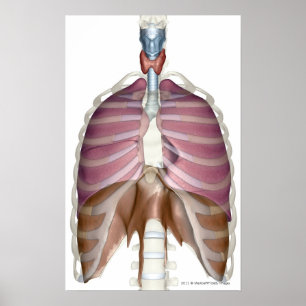

Human Heart Chest Anatomy Print

Prijs€ 23,90